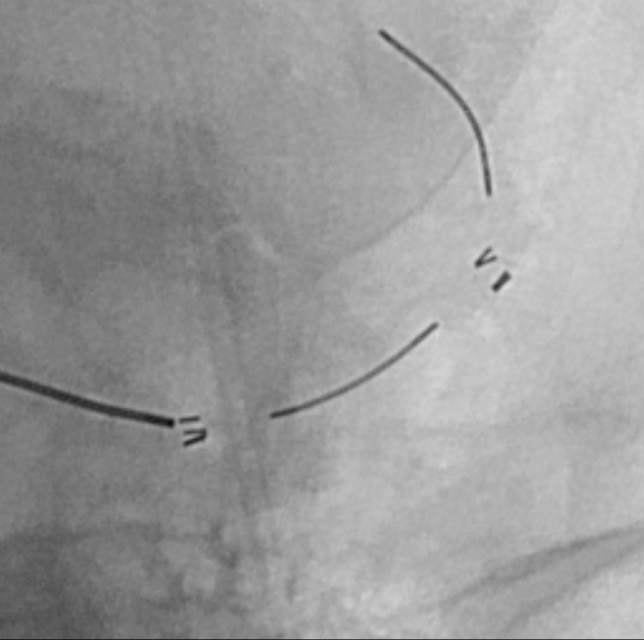

不干预吧,毕竟残存了一些功能障碍,还可能存在再次卒中的风险。通过多学科诊疗(MDT)和脑血管造影(金标准)后,进一步确认了狭窄的存在,左侧大脑中动脉上干血管存在重度狭窄,下干轻度狭窄。手术的难度在于狭窄的部位处于血管弯曲的部位,另外还要为下干预留日后可能干预的空间。

手术顺利完成,狭窄改善,血管直径基本恢复正常。